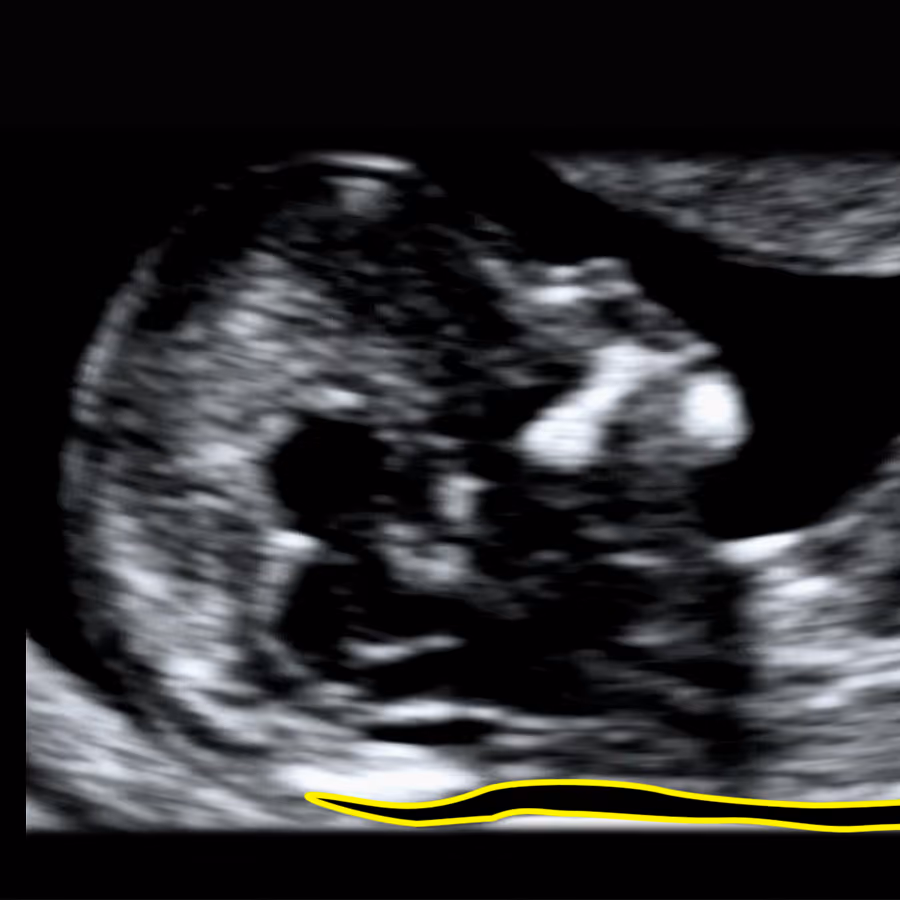

Nuchal translucency (NT) refers to the subcutaneous fluid-filled space between the fetal skin and the soft tissues overlying the cervical spine, visible on ultrasound in the first trimester. A small NT is a normal developmental feature, but an increased NT measurement may indicate chromosomal abnormalities, genetic syndromes, cardiac defects, or other structural anomalies. Assessment of NT provides an important early marker of overall fetal wellbeing.

Nuchal translucency (NT) is a small fluid space at the back of the baby’s neck, seen on early ultrasound. Every baby has some fluid, but when the NT is thicker than expected, it can sometimes be an early sign of genetic or structural problems. Measuring NT helps assess the baby’s wellbeing very early in pregnancy. An increased NT does not always mean there is a problem, but it is an important reason to carry out further tests to rule out possible conditions.

The NT measurement reflects the early development and balance of fluid within the baby’s tissues and circulation. It depends on the proper function of the heart, blood vessels, and lymphatic system, as well as the composition of the connective tissue. An increased NT may arise from temporary disturbance in fluid balance - for example, due to reduced cardiac function, delayed lymphatic drainage, or changes in tissue fluid permeability. Other biological mechanisms may also contribute, and some remain not yet fully understood.

The NT scan is an ultrasound in early pregnancy which measures the thin pocket of fluid at the back of your baby’s neck. This measurement helps estimate the chance of some chromosomal conditions (like Down syndrome) and certain structural problems, especially heart defects.

You lie on the couch and gel is placed on your tummy. The sonographer moves the probe over your abdomen to see the baby on the screen, checks the heartbeat and general development, and then measures the NT at the back of the neck.

As a simple rule of thumb, between 11 and 14 weeks an NT under about 3.5 mm is usually considered within the expected range. Measurements of 3.5 mm or more are often labelled “increased” or “high”, but in reality they represent an abnormal NT because they are above the 99th centile. At around 10 weeks’ gestation, the abnormal cut-off is lower, at about 2.5 mm, because the baby is still very small and NT is closely related to fetal size.